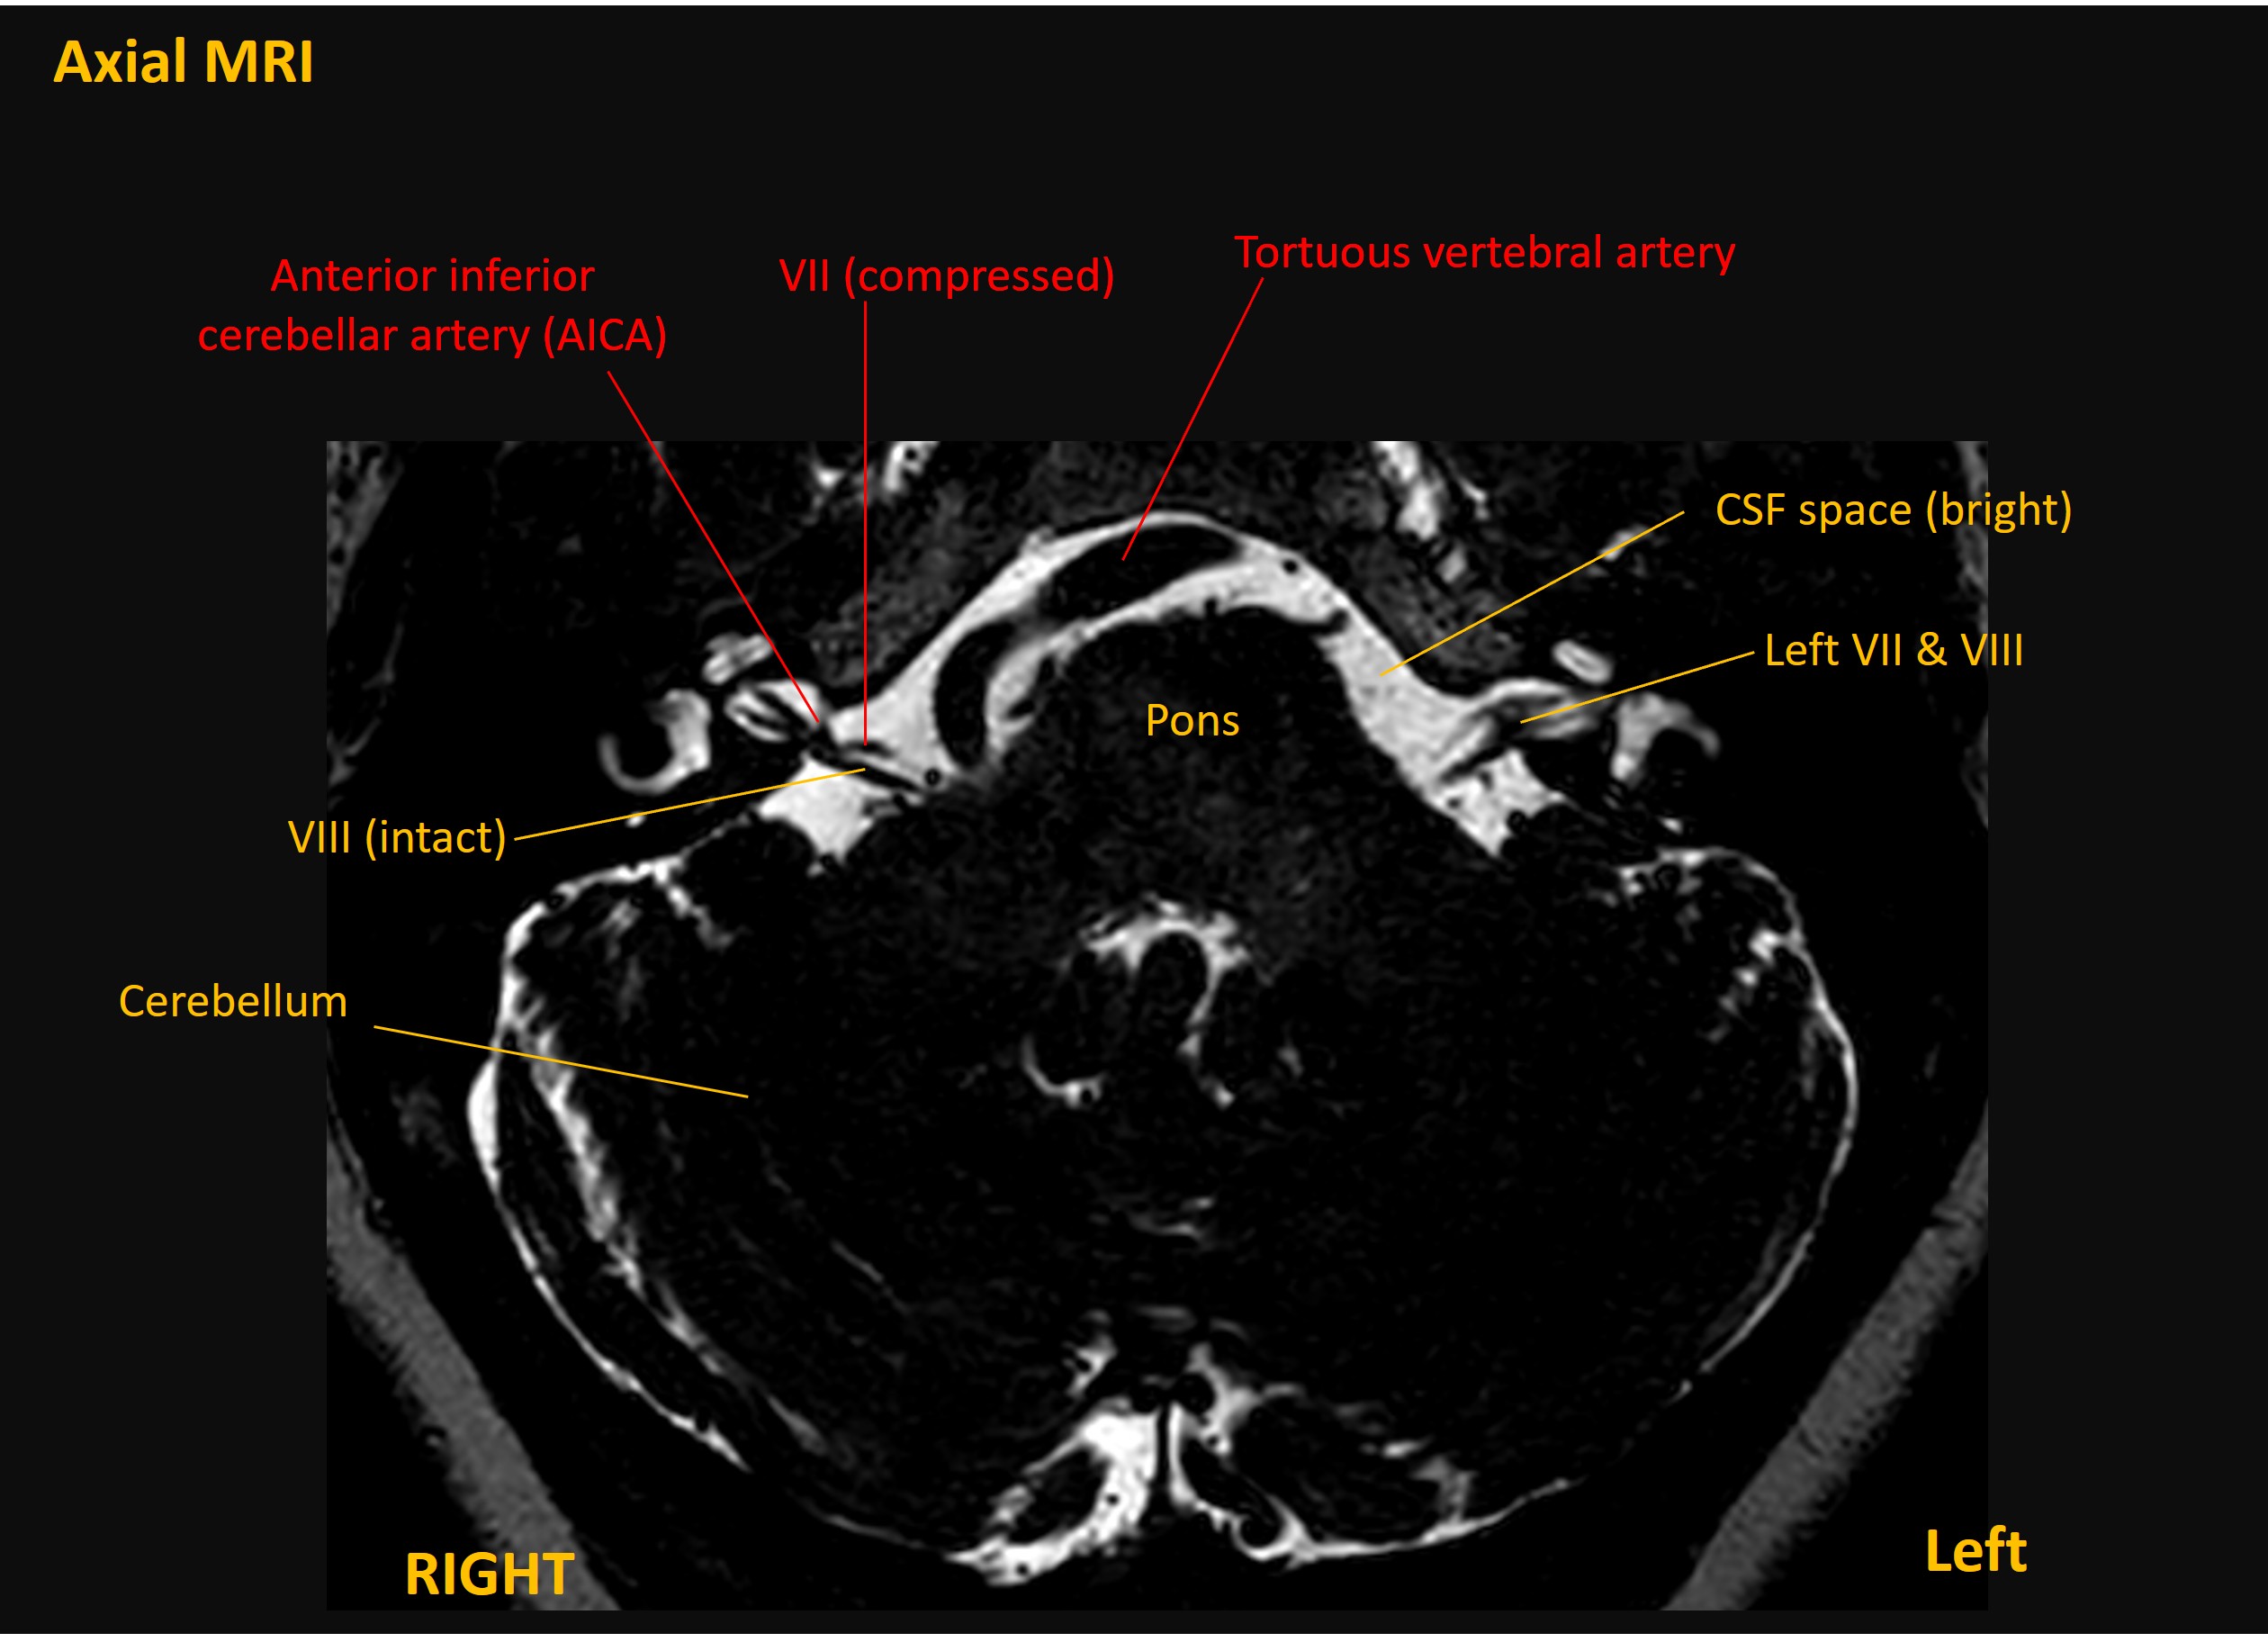

Hemifacial spasm was diagnosed. The patient underwent an MRI which showed neurovascular conflict – with the anterior inferior cerebellar artery (AICA) kinking the right facial nerve at its origin site in the inferior pons (MRI and illustration below).

Right hemifacial spasm due to neurovascular conflict between the facial nerve and the AICA, with sustained symptomatic benefit from botulinum toxin.